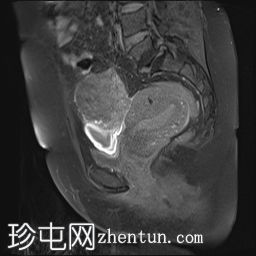

MRI

矢状位

T2加权像

可见子宫外腹腔内妊娠囊,内含胎儿组织。

该妊娠囊向后推移子宫,并与剖宫产瘢痕凹陷处紧密相连。

该妊娠囊与相关肠袢无法分离。可见其与性腺血管密不可分,且性腺血管明显突出。

胎盘位于妊娠囊后方,紧贴子宫前壁。

沿妊娠囊下缘可见一处异质性局灶性积液,最大轴向尺寸约为 8.4 × 5.5 cm,T1 加权像呈异质性高信号,T2 加权像呈异质性中等信号,T1 脂肪抑制序列未见信号下降,提示为血液成分。该积液压迫膀胱。

可见周围脂肪间隙呈条索状改变。

左侧卵巢无法辨认。

右侧卵巢未见实性或囊性肿块。

子宫体积增大,后倾,子宫内膜厚度约 1 cm,子宫下段前壁可见局灶性变薄(既往子宫瘢痕)。子宫连接区完整,未见肌层肿块。可见子宫内膜腔边缘有血性分泌物。